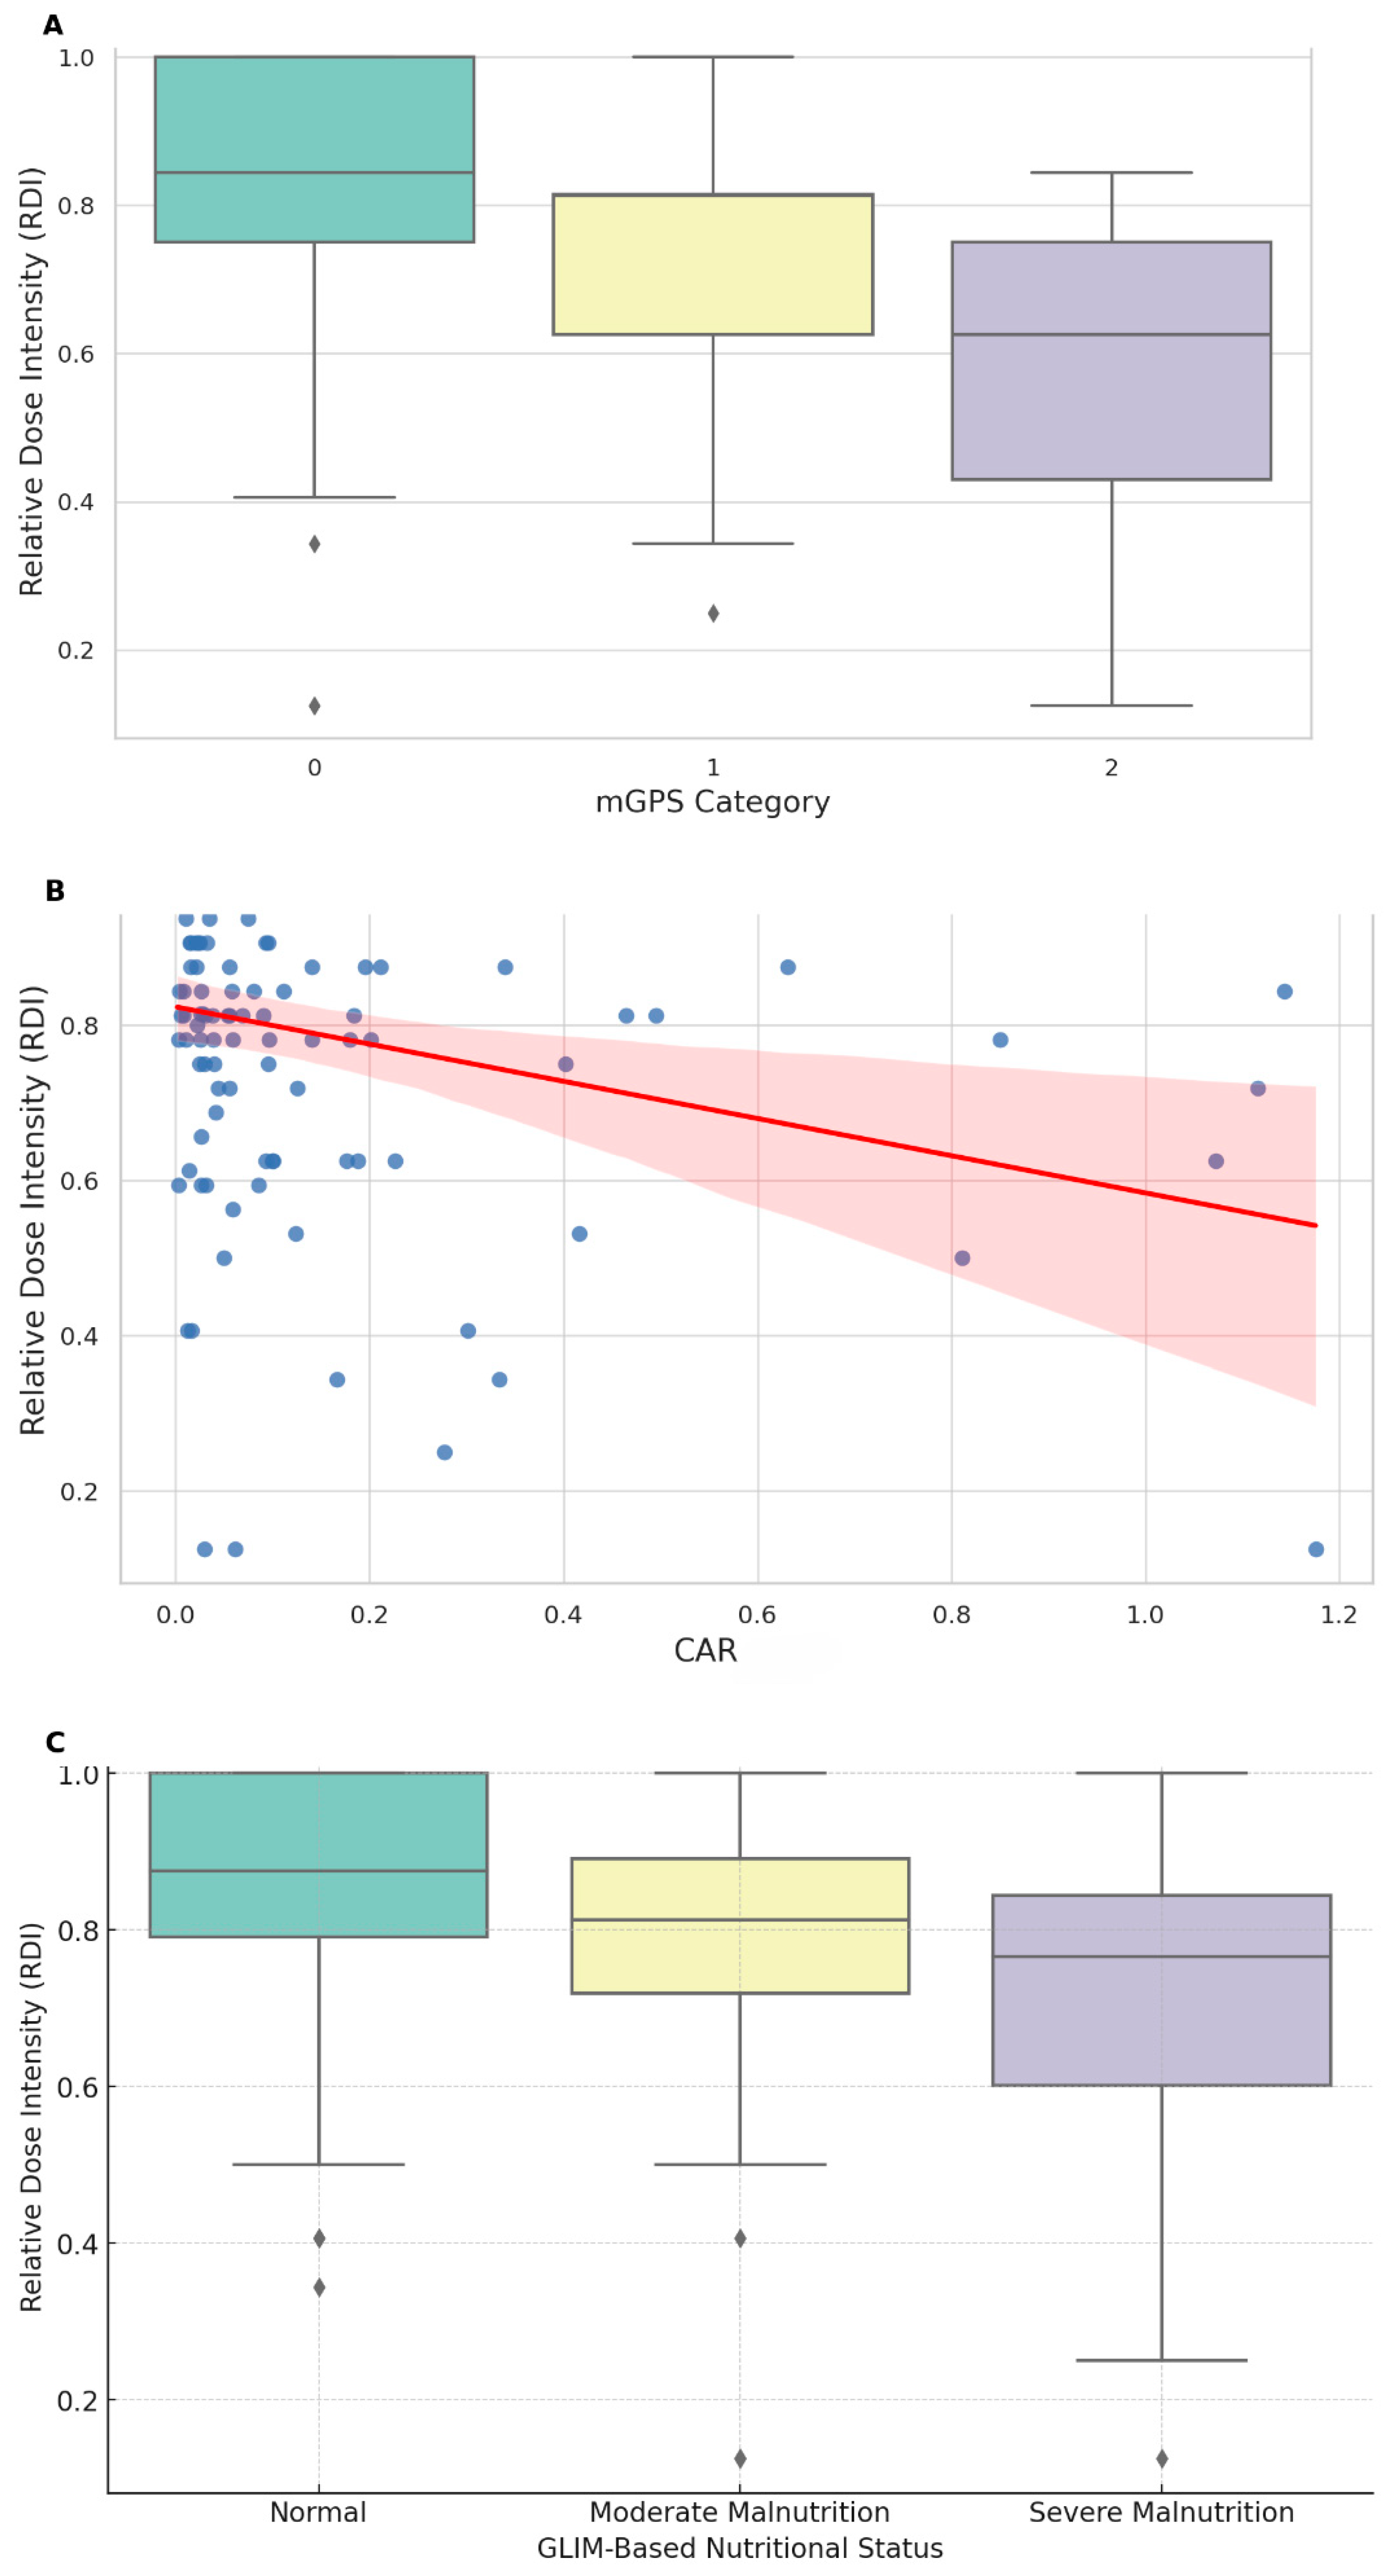

| mGPS | |||||

| Low risk | 46 (90.2%) | 33 (76.74%) | 16 (72.73%) | 95 (81.90%) | 0.814 ± 0.188 |

| Intermediate risk | 5 (9.8%) | 7 (16.28%) | 5 (22.73%) | 17 (14.66%) | 0.710 ± 0.218 |

| High risk | 3 (6.98%) | 1 (4.55%) | 4 (3.45%) | 0.555 ± 0.314 | |

| GLIM criteria | |||||

| No malnutrition | 51 (43.97%) | 0.844 ± 0.173 | |||

| Moderate malnutrition | 43 (37.07%) | 0.771 ± 0.208 | |||

| Severe malnutrition | 22 (18.97%) | 0.702 ± 0.232 | |||